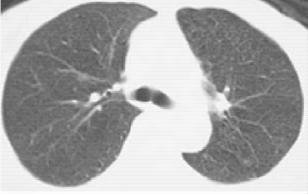

浸润型肺结核多见于成年人,起病缓慢,临床症状视其病灶范围及人体反应性而定。早期及病灶较小者往往无明显症状及体征,常由健康查体时的胸部X线检查发现,显示为锁骨上下片状、絮状阴影,边缘模糊。当人体处于过敏状态且有大量结核菌进入肺部时,病灶呈干酪样坏死、液化,进而形成空洞及病灶的支气管播散(图1-2)。浸润型肺结核伴大片干酪样坏死灶时,常呈急性进展,出现严重毒性症状,临床上称为干酪性(或结核性)肺炎。干酪样坏死灶部分消散后,周围形成纤维包膜;或空洞的引流支气管阻塞,致使空洞内干酪物难以排出,凝成球形病灶,称为“结核球”(图1-3)。当病变处于炎症渗出、细胞浸润甚至干酪样坏死阶段,经恰当的抗结核化学治疗后,炎症吸收消散;遗留的细小干酪样病灶经纤维包围,逐渐失水、干燥甚至钙化,成为残留的结节状病灶,称纤维硬结病灶或临床痊愈。

图1-3 男性,20岁,体检胸片类圆形,左肺结核球